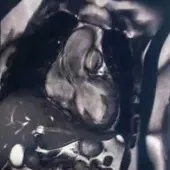

之后患者完善了冠脉CT及动态心肌SPECT检查。冠脉CT示:左前降支近段30%~50%狭窄,其余心外膜冠状动脉未见明显病变,同时可见到从心尖至侧壁的显著肌小梁化(图2)。患者SPECT回报:运动相左室显影清晰,左心扩大、部分下壁近心尖处见放射性缺损区,LVEF值36%;静息相与运动相比较,部分下壁近心尖处未见明显填充,呈不可逆性缺损,LVEF值35%。

图2. 冠脉CT结果